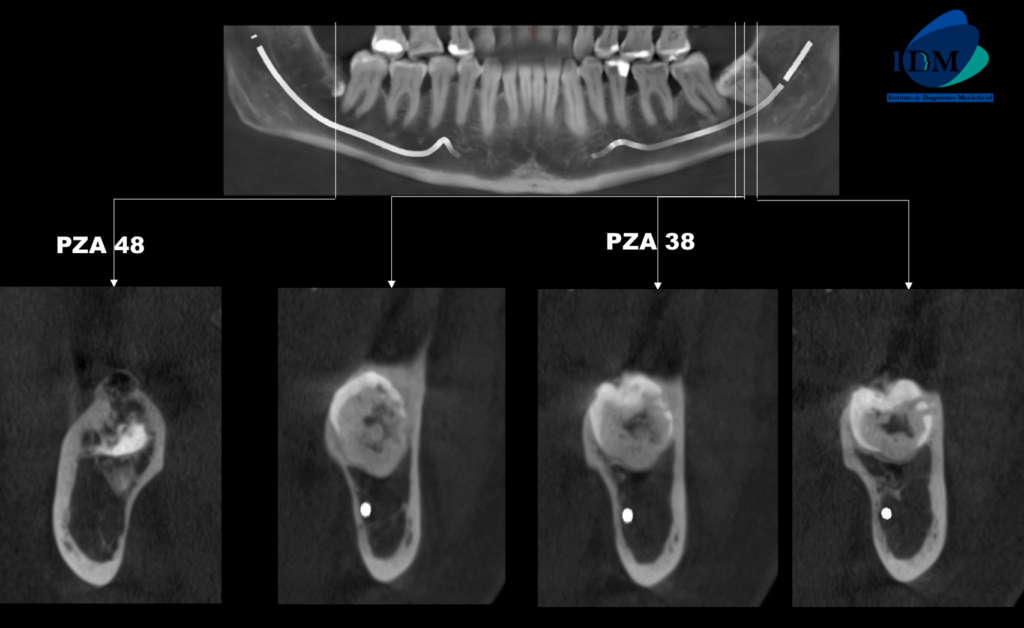

A la evaluación de la tomografía volumétrica (cone beam) en los cortes axiales (Figura 2), transaxiales (Figura 3) y tangenciales (Figura 4) se observa una reabsorción coronaria y radicular externa en tercio cervical de raíz distal (ameloclasia). Así como el remanente dentario de la pieza 48.

CORTES TRANSAXIALES